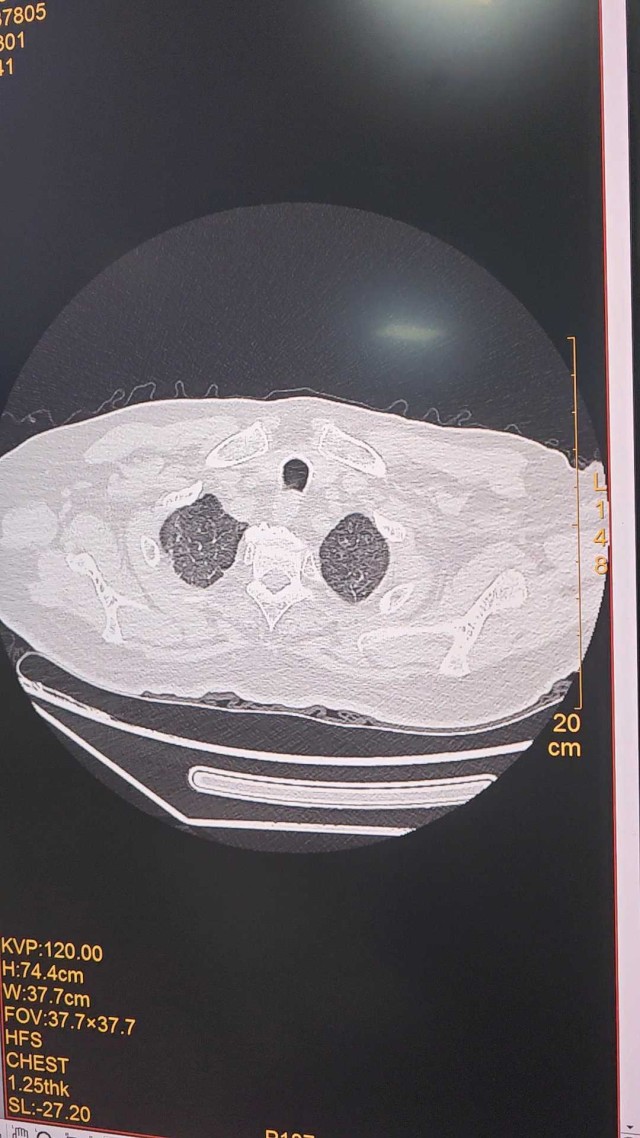

整个右侧胸腔被滚烫的铝水烧穿,多根肋骨骨折、碳化、坏死,背腹部和面部也有大面积烧伤……右肺完全暴露在外,被压缩到只剩一半的体积。这样的病人,还救得活吗?300℃ 铝水烧了 10 分钟,整个右胸都烧穿了时间拨回到 2024 年 9 月 26 日,下午 15 点,救护车的警笛声撕破了浙江大学医学院附属第二医院(文内简称「浙大二院」)解放路院区的平静。警笛声由远及近,停在了急诊的门口。不多时,一群人冲进急诊。「300 多度的铝水烧了 10 分钟,整个右胸都烧穿了!」负责转运的同事几乎是咆哮着喊出这句话。急诊医学科的许永安主任医师看到患者情形时,心下一惊。本该完整的右侧胸腔,现在成了一个焦黑的大洞,大